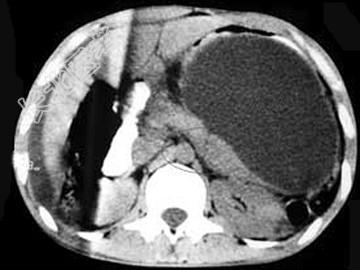

- 单项选择题男,33岁, 腹部外伤后2月余,腹部疼痛, 行CT扫描所见如图,最可能的诊断是 ( )

C、胰腺创伤性假性囊肿